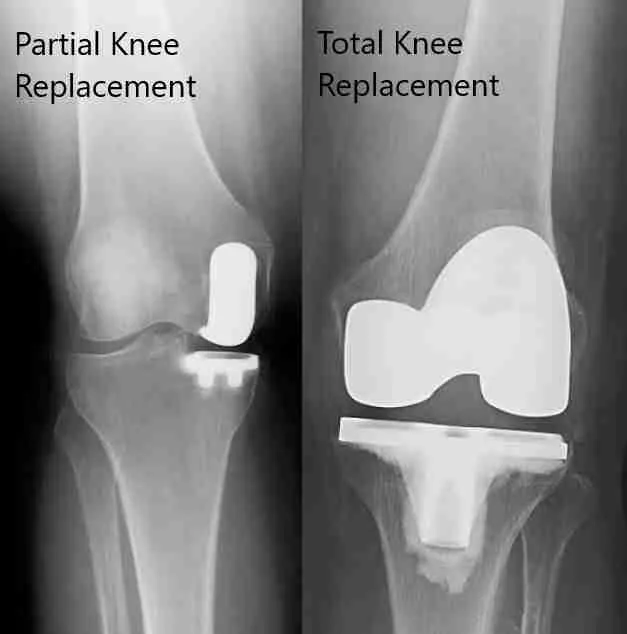

What is a knee arthroplasty? Knee arthroplasty is an [...]